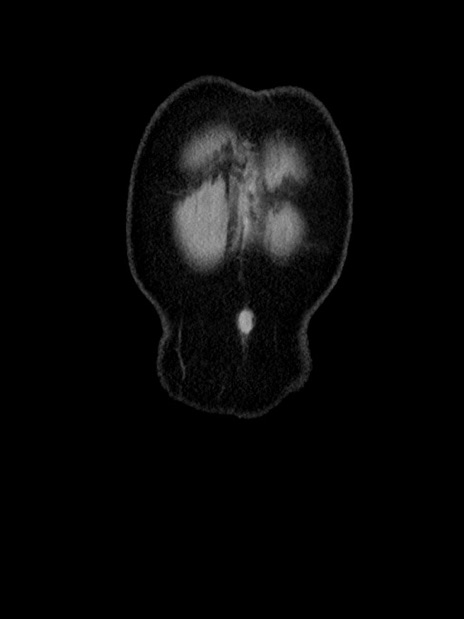

横断像